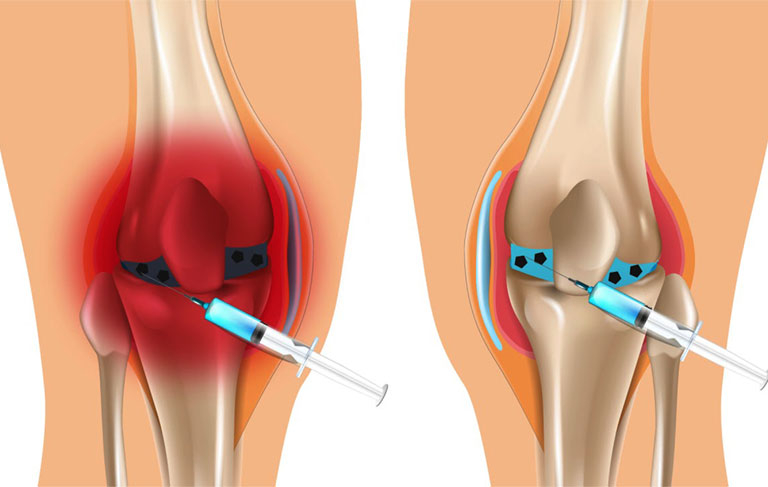

Axit hyaluronic là một thành phần quan trọng trong dịch khớp, giúp khớp hoạt động trơn tru hơn. Khi bị thoái hóa, lượng axit hyaluronic giảm sút, do đó bổ sung qua đường tiêm có thể giúp cải thiện tình trạng của khớp.

Thuốc Tiêm Điều Trị Thoái Hóa Khớp Gối

Singjoint là một giải pháp hiệu quả cho bệnh nhân thoái hóa khớp gối. Đây là loại thuốc tiêm chứa axit hyaluronic, giúp tái tạo độ nhớt của dịch khớp, từ đó giảm ma sát, giảm đau và cải thiện khả năng vận động của khớp gối. Việc tiêm Singjoint phải được thực hiện bởi bác sĩ chuyên khoa để đảm bảo an toàn và hiệu quả cao nhất.